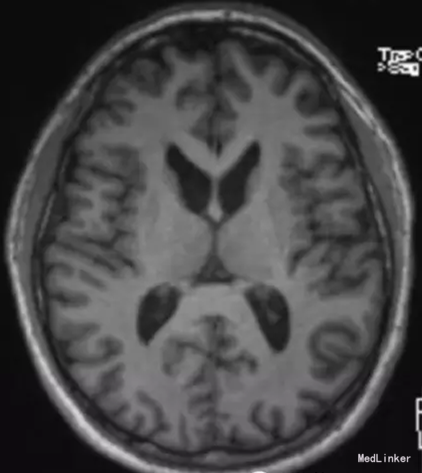

查体:进食性肌张力障碍、构音障碍,肢体肌张力障碍及舞蹈样动作。血清转氨酶及肌酸激酶水平升高。血涂片可见棘红细胞,肌肉活检提示肌病,影像学提示尾状核萎缩,遗传学检查发现复合杂合子新的VPS13A基因突变。